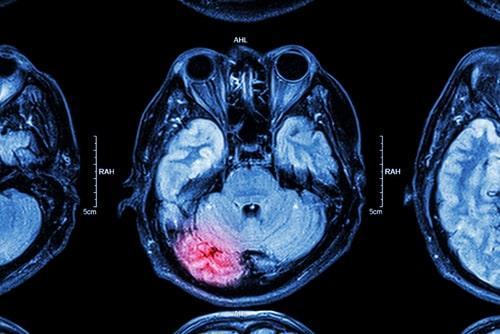

A traumatic brain injury or TBI involves damage to brain tissue resulting from a blow to the head or a strong jolt to the body that causes the brain to move around inside the skull. This may result in bruising of the brain, torn brain tissue, or serious bleeding, which can put pressure on the brain and cause additional damage. A mild traumatic brain injury may result in symptoms such as headaches, nausea, vomiting, fatigue, dizziness, blurred vision, ringing in the ears, confusion, temporary memory loss, or loss of consciousness. These symptoms will usually last for a short period of time, typically around a few days to a week.

Moderate or severe brain injuries can be much more serious, and they may result in some of the same symptoms as mild brain injuries, although these symptoms may persist for a longer period of time. A victim may also experience other long-term symptoms that affect their quality of life, such as chronic headaches, weakness in the body, loss of coordination, sleep disorders that result in difficulty sleeping or sleeping more than normal, slurred speech or difficulty expressing themselves, problems with concentration, impairments to hearing or vision, mood disorders such as anxiety or depression, personality changes involving anger or irritability, sensitivity to light or sound, continued memory loss, or seizures.

Multiple forms of medical treatment may be needed to address moderate or severe traumatic brain injuries. Surgery may be required to remove blood clots or dead brain tissue and relieve pressure on the brain. A person may need to take medications such as anticoagulants to prevent blood clots, anticonvulsants to address seizures, muscle relaxants to address muscle spasms, or antidepressants to treat mood disorders. Multiple forms of ongoing rehabilitative therapy may also be needed, such as physical therapy, speech therapy, psychological treatment, or occupational therapy.